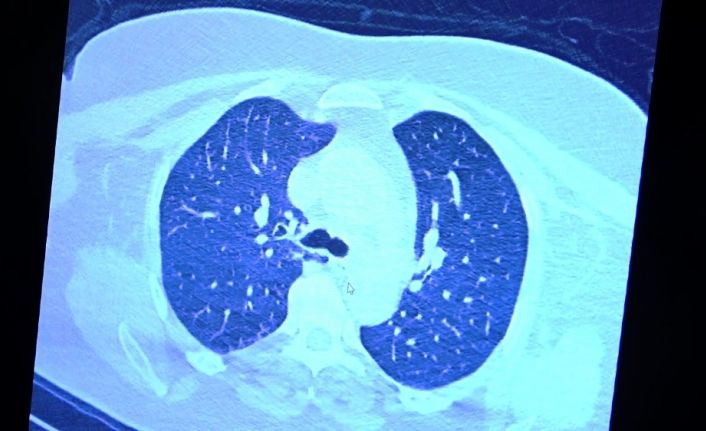

VM Medical Park Samsun Hastanesi’nde görev yapan Göğüs Hastalıkları Kliniği’nden Prof. Dr. Şevket Özkaya da bir hafta ilaç kullanmayan bir pozitif hastanın akciğer tomografisini inceledi. Hasta pozitif haldeyken ilk akciğer tomografisine bakıldı. Tomografide akciğerlerdeki tutulmanın az olduğu gözlemlendi. Akabinde aynı hastanın verilen ilaçları kullanmamış ve 1 hafta boyunca tedaviye uymamış haldeki akciğer tomografisine bakıldı. Sonuç ise ilaç kullanımının önemini ortaya çıkardı. Hastanın akciğer tomografisinde yaygın buzlu camların ve hava yollarının hava yerine ciddi şekilde sıvı ile dolduğu gözlemlendi.

Akciğer tomografisinde oluşan değişim ile ilgili bilgi veren Prof. Dr. Şevket Özkaya, "Ekranda 55 yaşında bir kadın hastamızın filmini görüyorsunuz. Bu kadın hastamız acil servisimize ateş şikâyetiyle geldi ve korona virüsünden şüphe ettik. Testini yaptığımızda ise testin sonucu pozitif geldi. Tomografi çektiğimiz zaman akciğerlerinde henüz ciddi bir tutulum görünmezken hastamız 55 yaşında olduğu için her an ilerleyebilir korkusuyla Sağlık Bakanlığımızın önerdiği ilaçları ve reçeteyi hastanemizden kendisine verdik. Hasta kendini evde karantinaya aldı fakat sonradan öğrendik ki tereddüt ettiği için ilaçlarını kullanmayarak kendini evde tedavisiz bırakmış. Yaklaşık bir hafta sonra aynı hasta acil servisimize bu sefer solunum yetmezliği şikâyetiyle geldi. Solunum yetmezliği gelişince hastanın akciğer tomografisinde ‘buzlu cam’ dediğimiz ve daha ileri konsolide alanların oluştuğunu gördük. Yaygın akciğer harabiyeti dediğimiz bir tablo oluşmuştu. Bu durumda hastada solunum yetmezliği olduğu için yoğun bakıma almak zorunda kaldık" dedi.